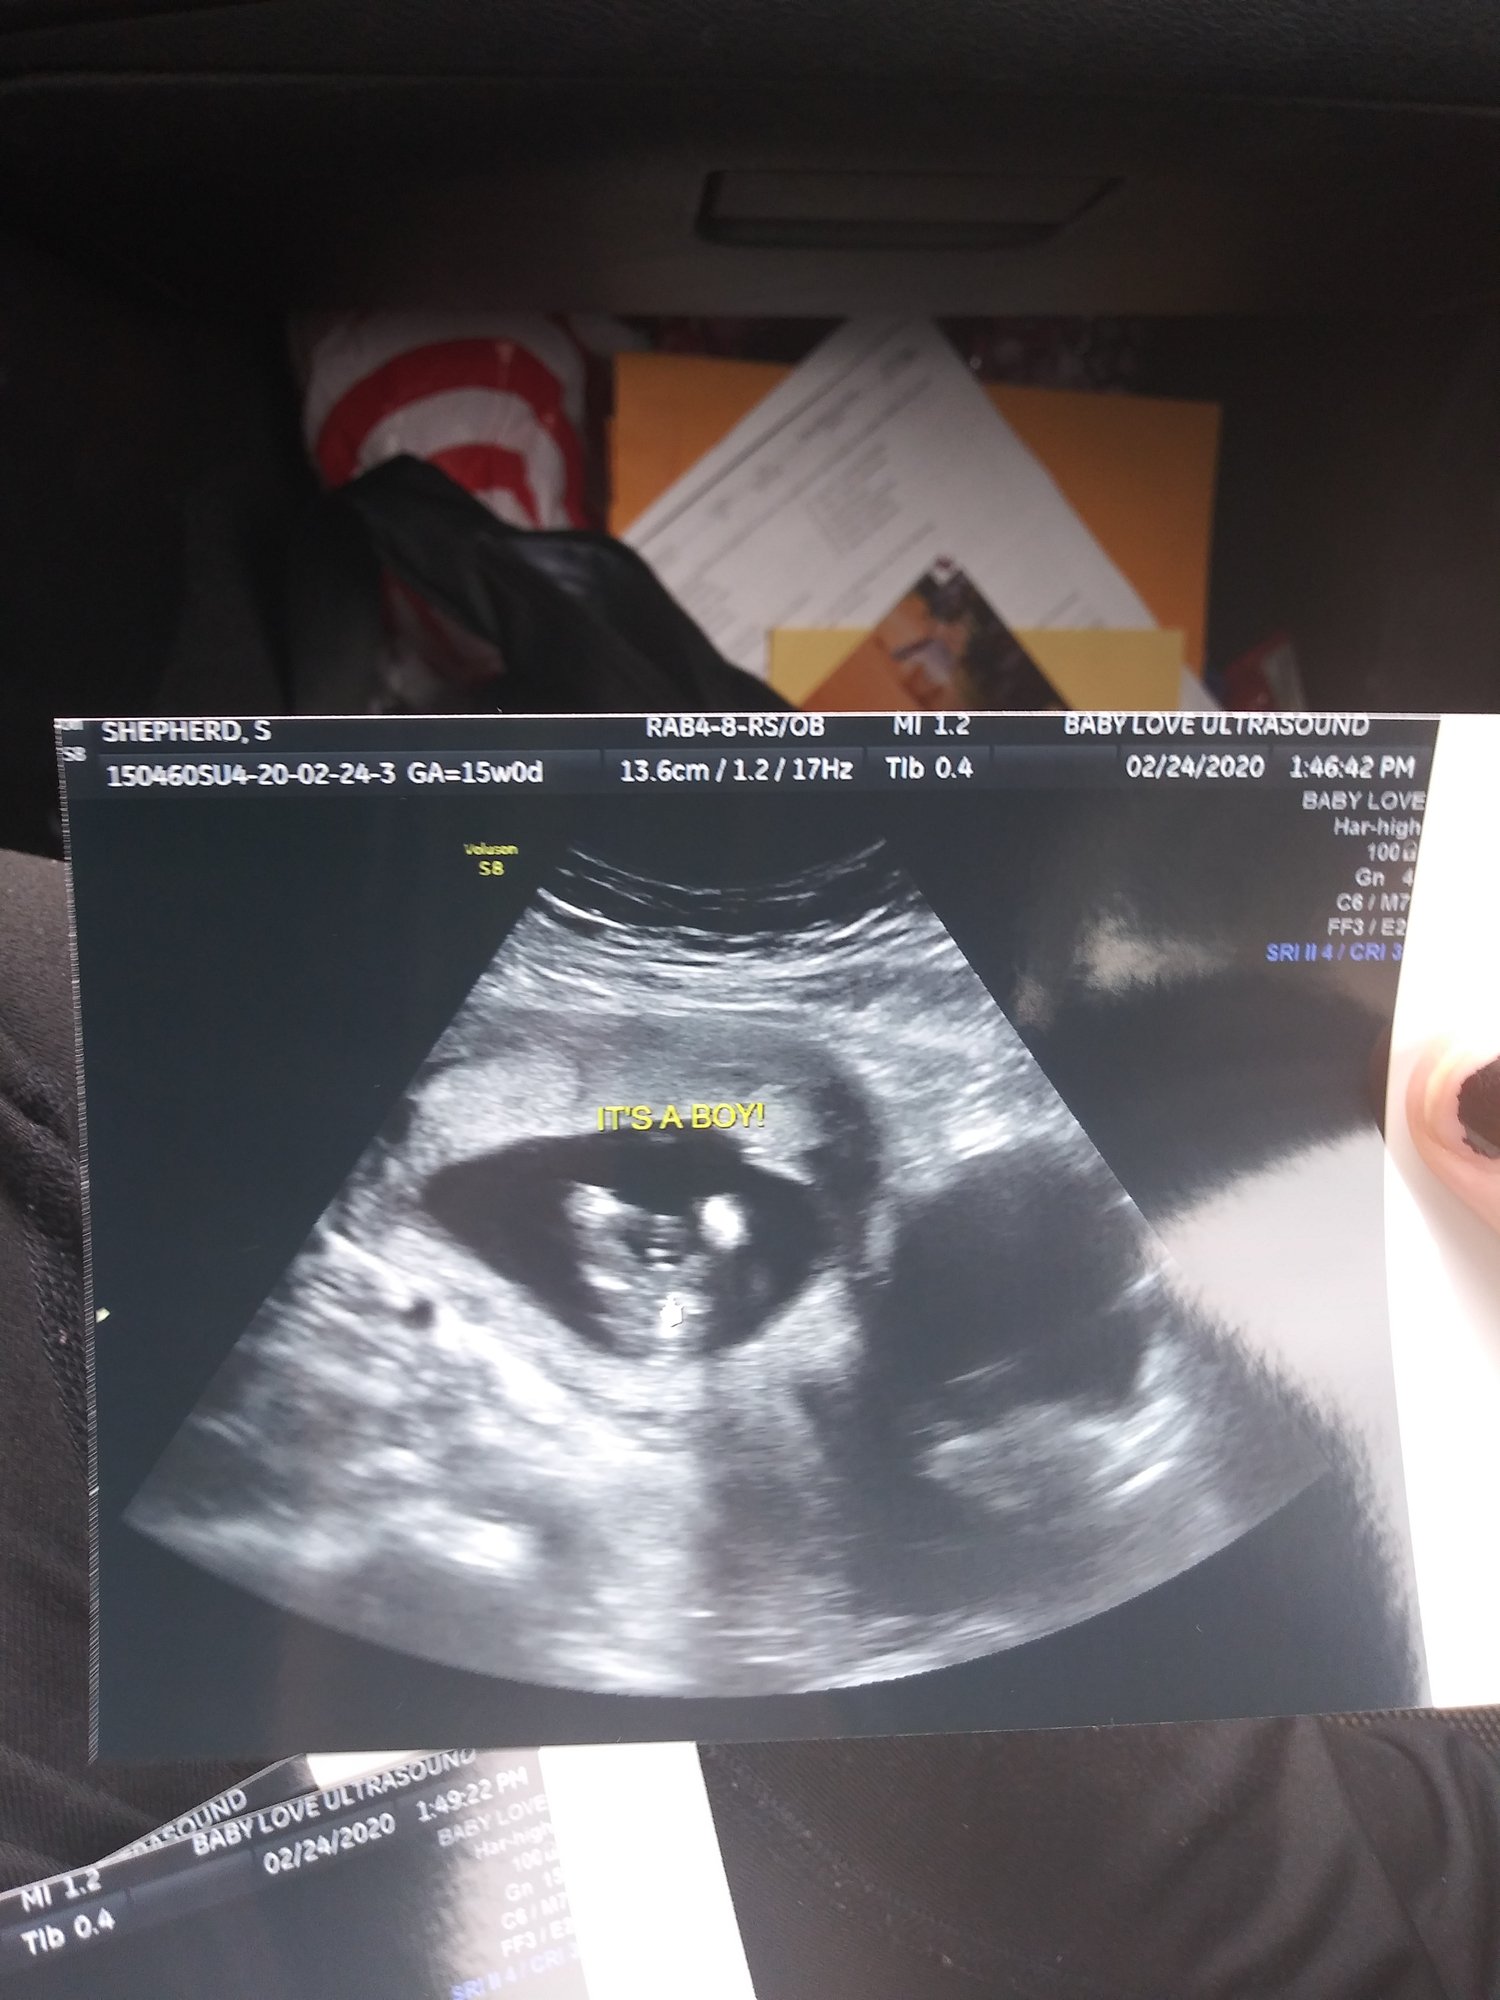

Due to some events that have happened. I canceled my gender screening for friday and moved it to today at 2pm. So I should know in a few hours what this baby is for sure.

Anyone want to take any guesses? my dad and sister say boy. My husband, kids, stepmom, grandma, and my mom all say girl.

He must be well endowed because as soon as the lady checked ahe instantly says "wow definitely boy parts,". So sneak peek was correct!

I'm excited to have another boy!

The nurse also said my placenta in anterior and thats why I'm not feeling him kick.